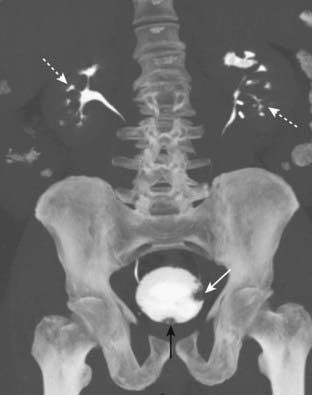

image Most malignant bladder tumors are transitional cell tumors. Transitional tumors may occur simultaneously anywhere along the uroepithelium from the bladder to the ureter to the kidney. The primary tumor appears as focal thickening of the bladder wall or may produce a filling defect in the contrast-filled bladder (Fig. 18-39).

Figure 18-39 Transitional cell carcinoma of the bladder, CT urogram.

There is a filling defect in the left lateral wall of the contrast-filled bladder (solid white arrow) representing a tumor. The defect at the base of the bladder (solid black arrow) is caused by the prostate gland. The calyceal collecting systems (dotted white arrows) are normal.

imageRecognizing the CT findings of lymphoma:

image Multiple enlarged lymph nodes. Pelvic lymph nodes are considered pathologically enlarged if they exceed 1 cm in their shortest dimension.

image Conglomerate masses of coalesced nodes. Bulky tumor masses that can encase and obstruct vessels.

image Lymphadenopathy will classically displace the aorta and/or vena cava anteriorly (Fig. 18-40).

Figure 18-40 Massive lymphadenopathy, lymphoma.

There is massive abdominal lymphadenopathy occupying most of the abdomen (solid white arrows) and displacing the kidneys (K) laterally and the aorta (A) anteriorly far from its normal location next to the spine (solid black arrow). The patient had non-Hodgkin lymphoma.